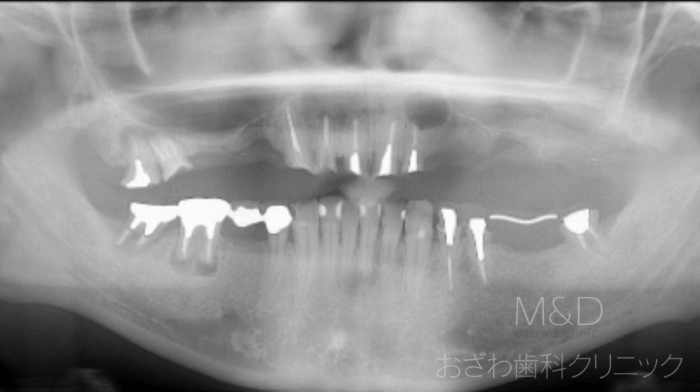

術前

主訴:上の入れ歯が落ちてくる、噛めない、差し歯が取れた、左上の前の歯茎が腫れる(歯根破折)右下奥歯の歯茎が腫れる、左下のブリッジが外れた

上顎残存歯の抜歯、左上2番巨大な歯根嚢胞摘出+人工骨移植、GBR

右側サイナスリフト(上顎洞底挙上術:上顎洞が近心前方に発達しているため)+GBR(歯槽骨欠損のため)

上顎7本 (4本で即時負荷、その後段階的にインプラント追加)下顎5本インプラント